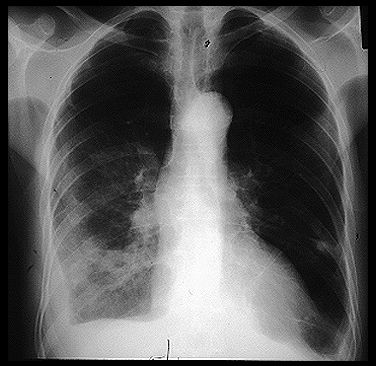

Tràn mủ màng phổi trên hình ảnh

Tràn mủ màng phổi là sự tích tụ mủ trong khoang màng phổi. Trong trường hợp hiếm hoi, viêm mủ màng phổi có thể xảy ra sau khi chọc kim xuyên qua thành ngực để rút chất dịch trong khoang màng phổi để chẩn đoán bệnh, điều trị. Mời các bạn cùng eLip tìm hiểu những thông tin về hội chứng này dưới đây nhé!

Viêm mủ màng phổi thường gây ra bởi một bệnh nhiễm trùng lây lan từ phổi. Nó dẫn đến sự tích tụ mủ trong khoang màng phổi.

Có thể có một ít dịch hoặc nhiều bị nhiễm bệnh. Chất lỏng này gây áp lực lên phổi.